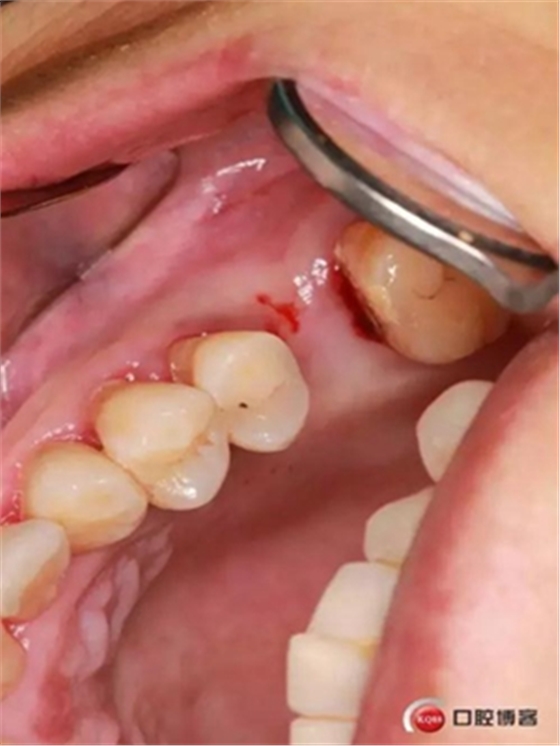

大家好,我是梁老師的助理小依。由于梁老師每天手術(shù)檔期安排較滿,加上經(jīng)常出差講課,沒有時間整理病例 。為了方便大家更及時的了解梁老師最新手術(shù)動態(tài),以后將由我為大家整理并推送梁老師最新經(jīng)典案例。案例文字旁白少,但圖片會盡量完整展示手術(shù)全過程,供大家學(xué)習(xí)參考。有任何問題,可以留言,梁老師會親自為大家解答。感謝大家對梁老師的支持和關(guān)注!